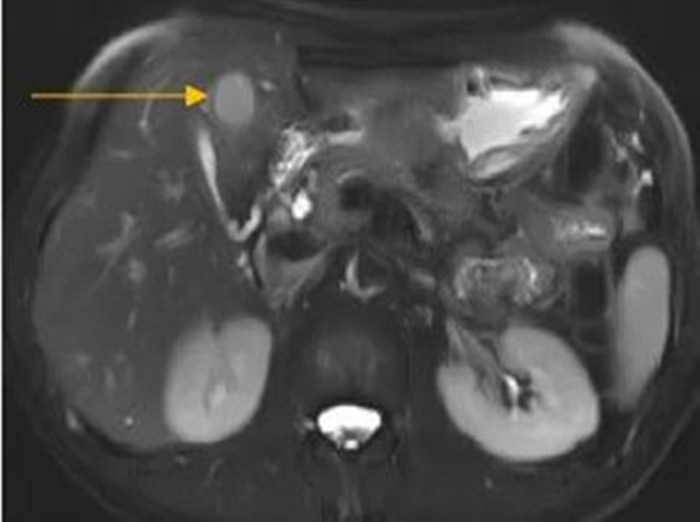

住院后經(jīng)胸腹部CT檢查,提示周先生胃部巨大腫塊穿破胃腔,可能累及到結(jié)腸,同時合并有胃旁淋巴結(jié)轉(zhuǎn)移、肝臟的轉(zhuǎn)移??吹竭@個檢查報告后,周先生和他的愛人一下子就泣不成聲了。

治療前的腹部CT提示胃

治療前肝臟的轉(zhuǎn)移灶